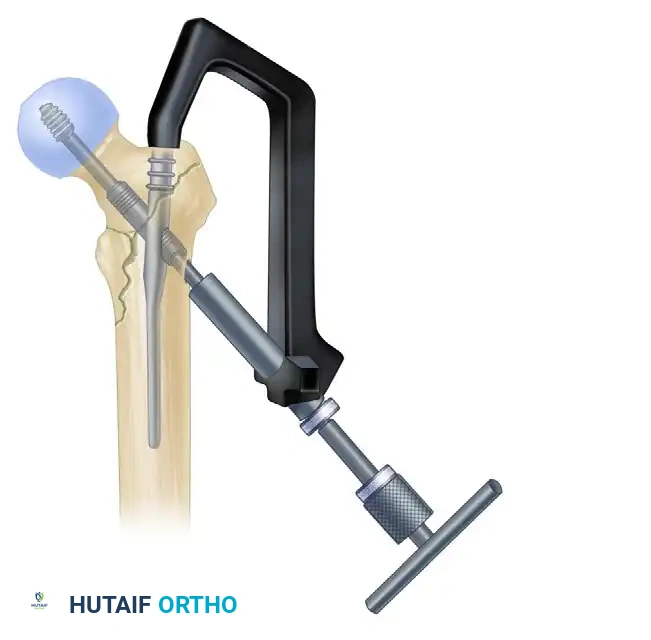

5. Lag Screw Placement and Compression

Achieving optimal lag screw placement is the most critical factor in preventing mechanical failure (cut-out). The goal is a Tip-Apex Distance (TAD) of less than 25 mm.

- Evaluate Version: Check the version of the nail on the lateral fluoroscopic view. The version is correct when the nail, the drill guide, the femoral neck, and the femoral head are all perfectly collinear.

- Make a small stab incision laterally through the skin and fascia lata corresponding to the targeting guide. Place the appropriate drill sleeve assembly down to the lateral cortex of the femur.

- Advance a threaded guide pin through the sleeve, up the femoral neck, and into the femoral head. Stop when the pin is within 5 mm of the subchondral bone.

- Confirm appropriate center-center position in the femoral head on both AP and lateral views.

- Measure for the length of the lag screw using the calibrated measuring device over the guide pin.

- Set the lag screw reamer to a depth 5 mm less than the measured length of the guide pin to prevent inadvertent joint penetration. Ream the lateral cortex and the lateral aspect of the femoral head.

- If the patient has dense, non-osteoporotic bone (e.g., a young patient with a high-energy mechanism), use a tap to prepare the thread path. In standard osteoporotic bone, tapping is generally unnecessary and may decrease screw purchase.

- Insert the lag screw over the guide pin until the threads are fully engaged in the subchondral bone of the femoral head.

- Use the centering sleeve insertion device to advance the centering sleeve over the lag screw shaft, locking it into the nail.

- Applying Compression: Before applying compression, release the traction on the fracture table. This allows the fracture fragments to settle. Insert the compression screw through the top of the nail and apply the desired amount of linear compression across the fracture site.